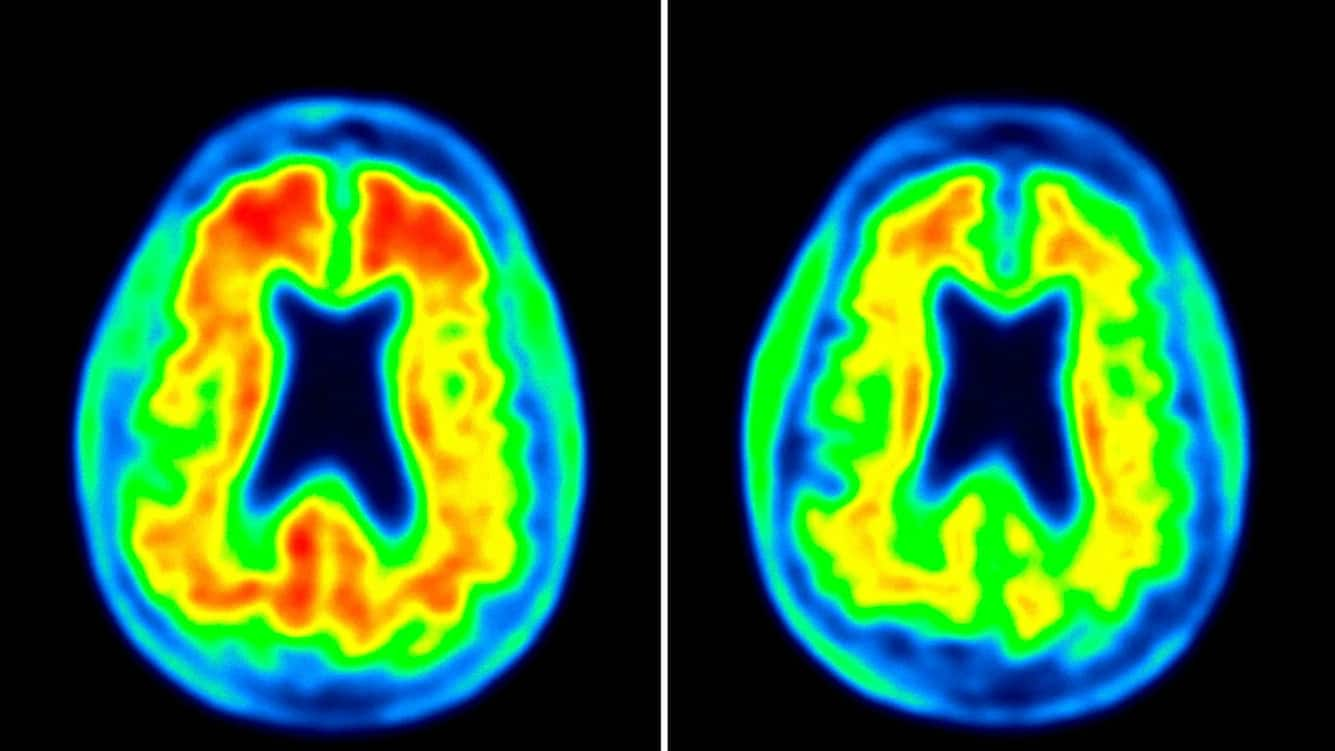

Aducanumab ist ein Heilmittel des Biotech-Konzerns Biogen, das viel Hoffnung weckt: Erstmals könnte eine Arznei nicht nur die Symptome der Alzheimer-Erkrankung mildern, sondern sogar den Krankheitsverlauf zu beeinflussen, so die ersten Anzeichen.

Der Wirkstoffkandidat Aducanumab hat eine beispiellose Geschichte hinter sich. Im März 2019 wurden die klinischen Studien gestoppt, weil es unwahrscheinlich schien, dass sich das Medikament als wirksam erweisen würde. Im Oktober kam es zu einer ersten Kehrtwende, als eine erneute Analyse der Daten den Schluss zuliess, dass sich das Medikament womöglich doch als wirksam herausstellen könnte. Die FDA und das Unternehmen einigten sich in der Folge auf einen Modus, wie die Daten zu lesen seien.